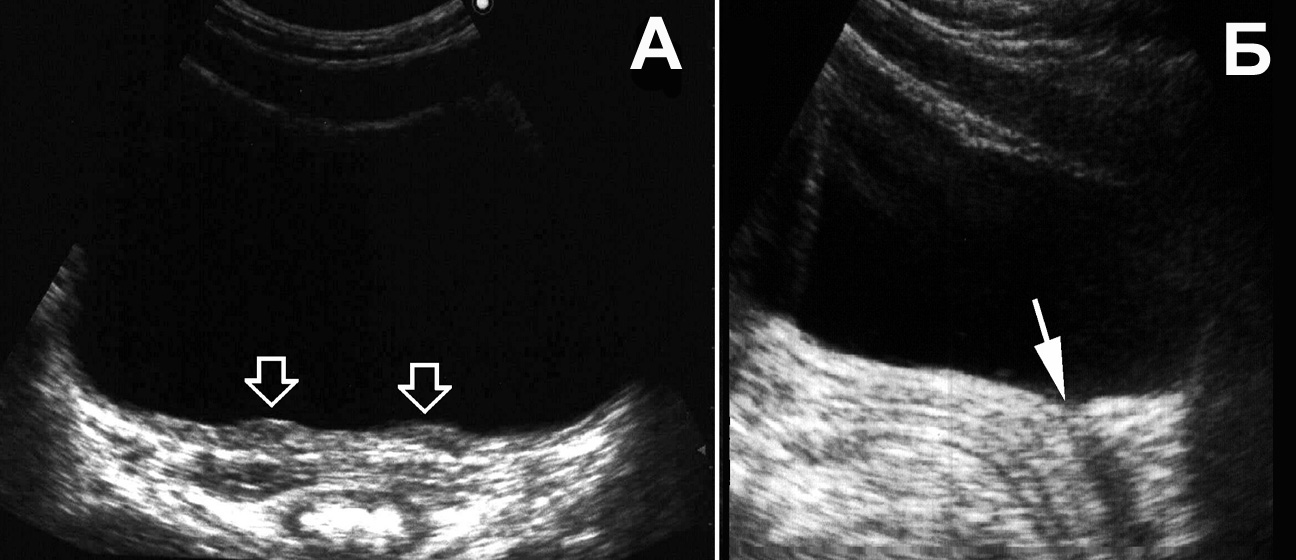

Рис. 1. Сонограмма мочевого пузыря мужчины в норме. Остаточный объем мочи с достаточной для практики точ¬но-стью можно определить по формуле a х b x c x 0,57 [50]. (Поперечное [A] и продольное [Б] сканирование, конвексный датчик 5 МГц, “Logiq-500”).

Рис. 16. Мочевой пузырь при цистите, лейкоцитурии. Определяется горизонтальный уровень нежной эхоструктуры (обозначен стрелкой), изменяющий свою форму и локализацию при перемене положения тела. (Поперечное сканирование, А − в положении пациента на спине, Б − на левом боку. Конвексный датчик 5 МГц, “Logiq-500”).